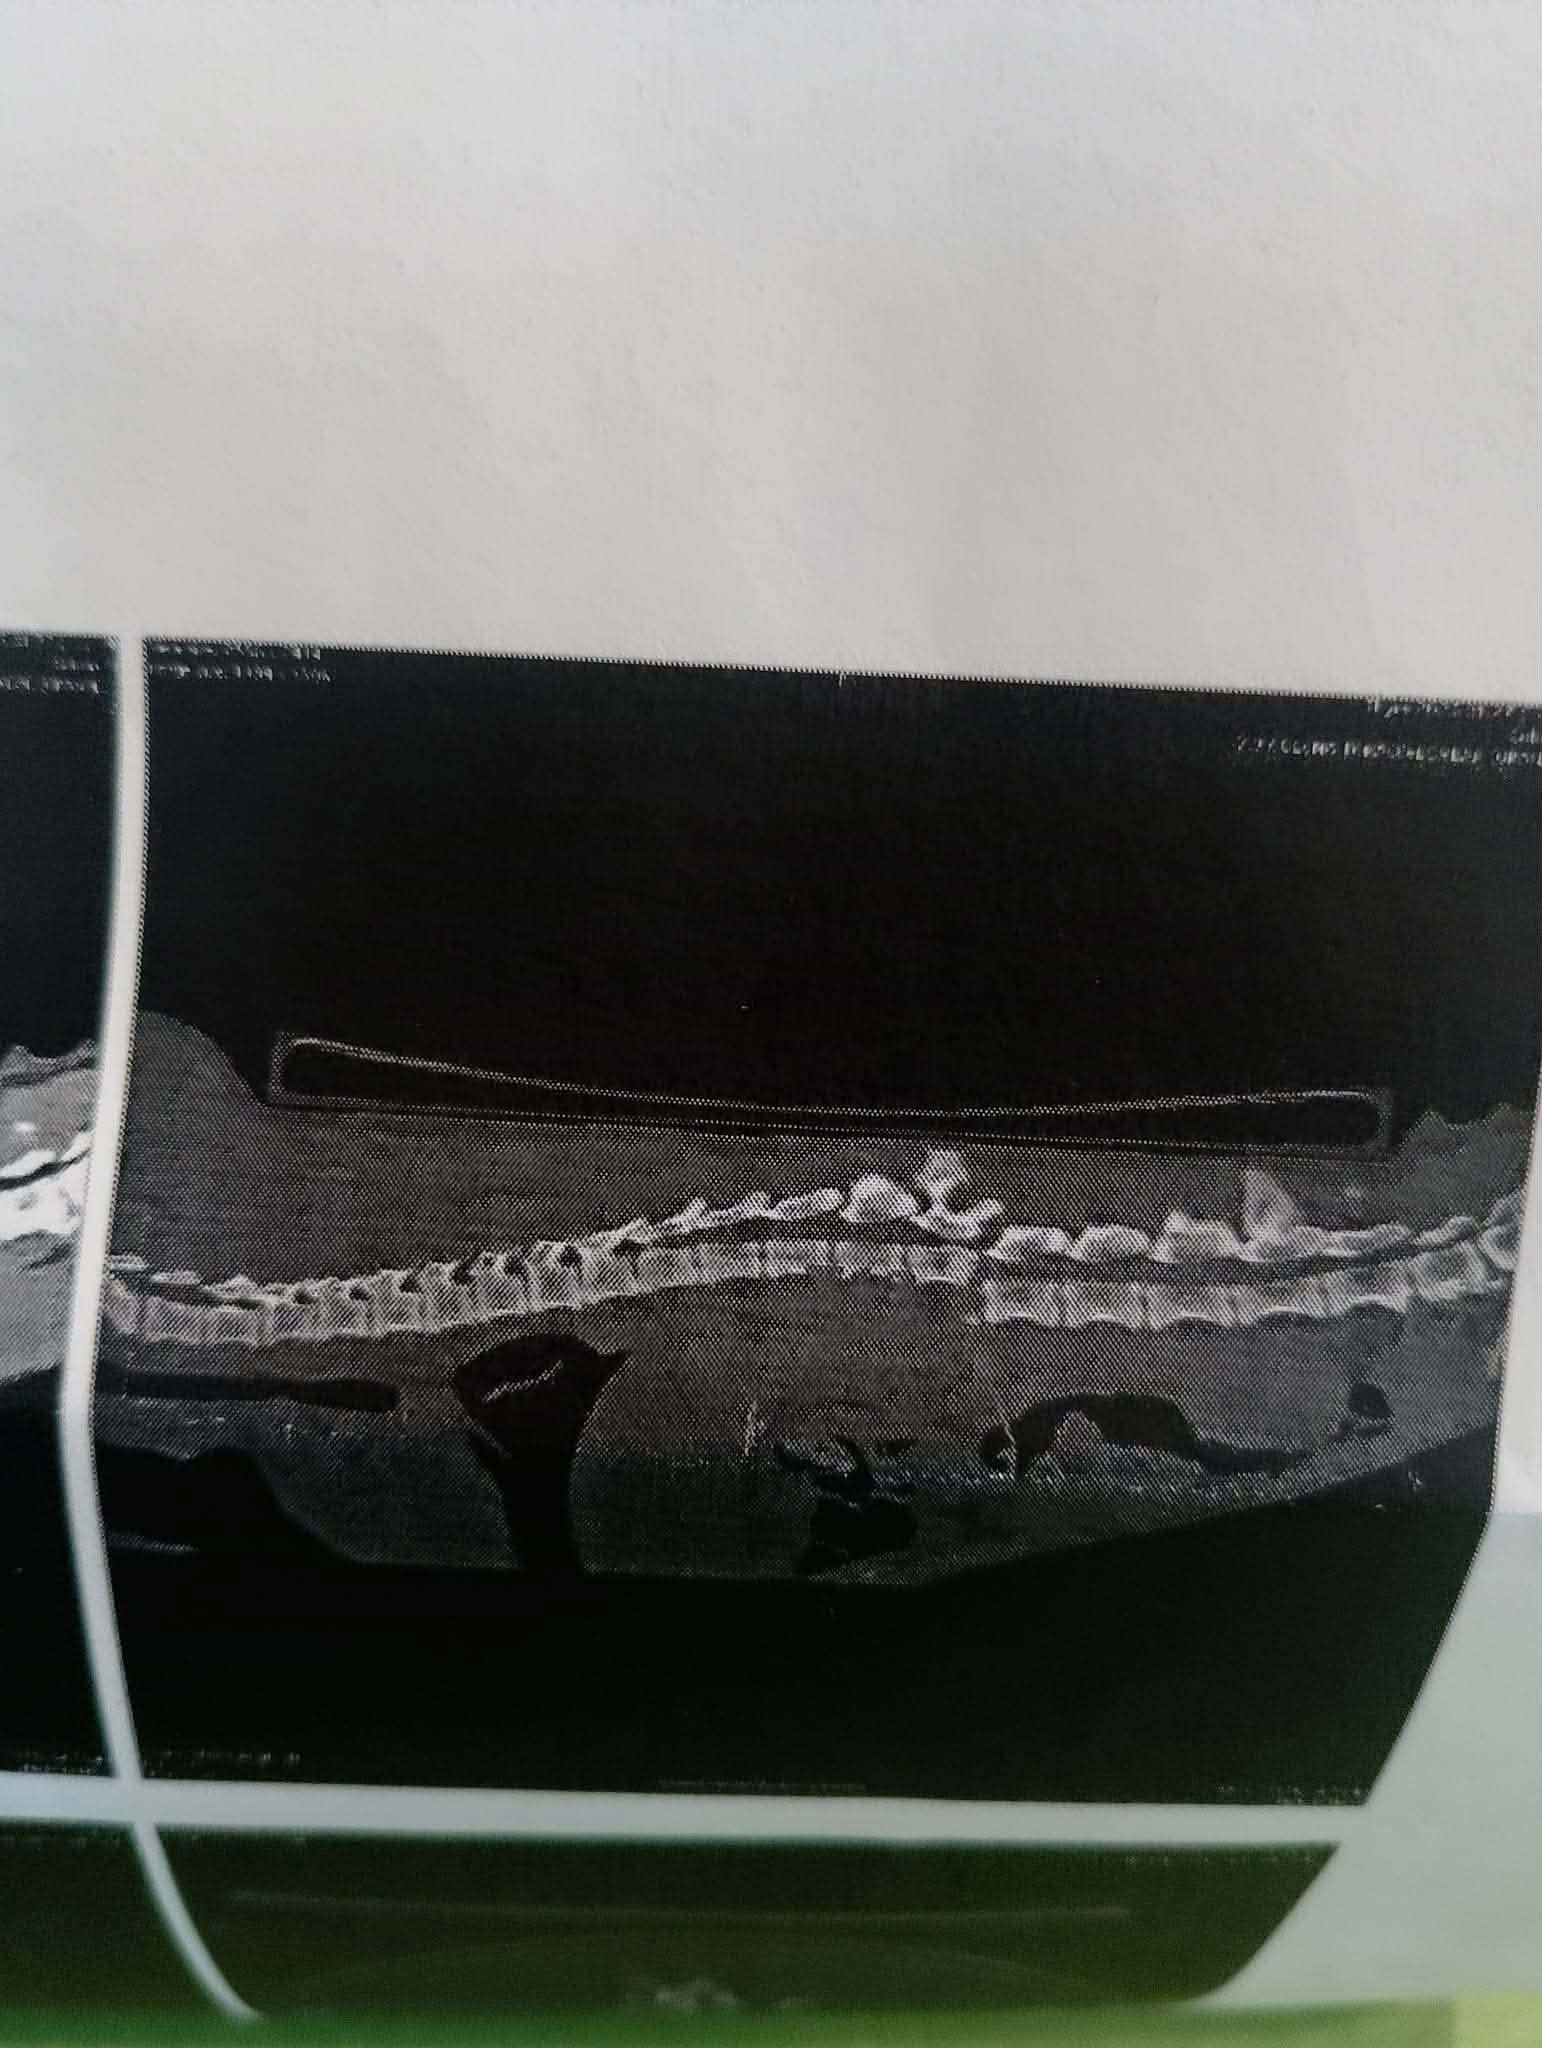

Thyra é uma linda Dogue Alemão e era jovem com toda a vida pela frente quando caiu e partiu a coluna. Esta é uma lesão devastadora e mudou para sempre a vida dela e da sua família amorosa. Terão sempre contas de veterinário e a Thyra terá sempre dificuldades. Mas é amada e a família pediu-nos um pouco de ajuda. Pagámos 133 euros por contas que não conseguiam pagar.

Thyra